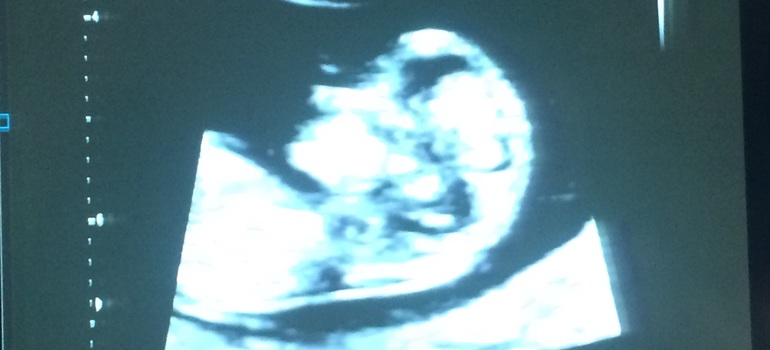

Все в норме... И носик наш, папин видно))) и со складкой все в норме))) ну и срок 12 недель и 1 день))) хотя по месячным 11 и 5... ПДР поставили на 29 февраля))))) Приятно удивила жк, наличием современного УЗИ и большого телика над головой, где все рассказывают и показывают. Здорово в общем)))) настроение супер))) чего всем и желаю😘😘😘😘😘

Я сегодня и испугаться не успела... Дети у бабушки ночевали сегодня))))) В сад она отводила... Ну естественно, после будильника решили поваляться, раз малышни нет... И конечно, проспали все на свете))) бегом бегом.... А в жк ни очередей, ни ругани... Сразу и зашла)) 56 мм уже))) прикольно так, пинается во всю, только не чувствую еще конечно)))